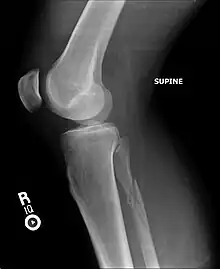

Maisonneuve fracture

| A Maisonneuve fracture with arrows marking the location of the two fractures | |

A Maisonneuve fracture is an injury at the ankle with an associated break of the lower leg near the knee.[5] The ankle injury involves a tear of the ligament connecting the two bones of the lower leg, the tibiofibular syndesmosis.[5] There may also be a break of the medial malleolus or rupture of the deltoid ligament of the ankle.[3] Symptoms typically include tenderness over the medial ankle and outside aspect of the upper part of the lower leg.[1]